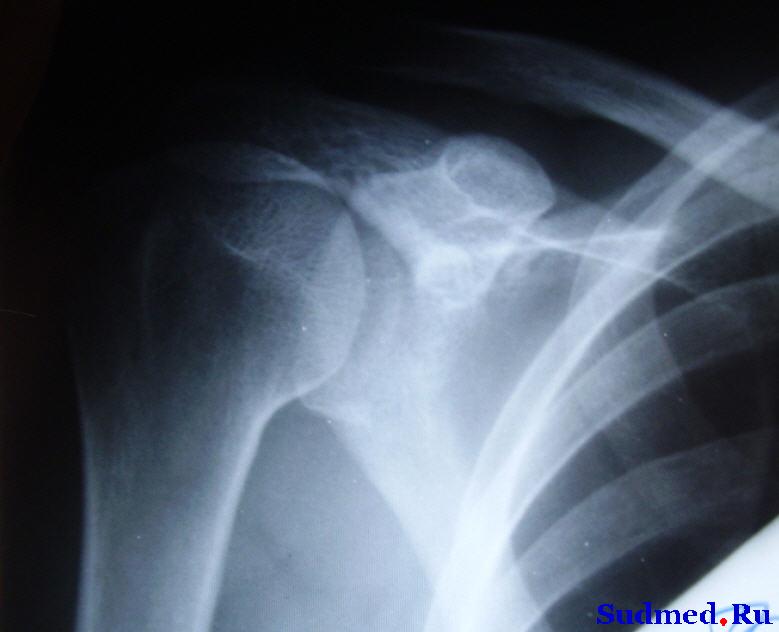

Был сделан один снимок правого плеча. Приложение прилагается.

Эскизы прикрепленных изображений

Судебная медицина - Прикрепленное изображение

3. По снимку ничего сказать не могу - очень жесткий и не четкий (результат сканирования рентгенограммы?).

Может быть кто-то из коллег что-то узрит.

Снимок бы конечно как-то бы получше - ну ничего не видно. Цифровиком против источника света сфотать, тогда и можно что сказать будет. А вообще с такими диагнозами обычно через 10 дней еще контрольные рентгенограммы делают обычно. Вот они-то более информативны.